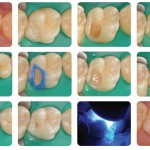

E’ ancora necessario abbattere lo smalto non sostenuto?

Compositi Nanoriempiti a bassa contrazione: è ancora necessario abbattere lo smalto non sostenuto? Studio clinico randomizzato

Candidato: MARCO CUPPARI

Relatore: NICOLA SCOTTI

INTRODUZIONE

Lo scopo di questo studio...